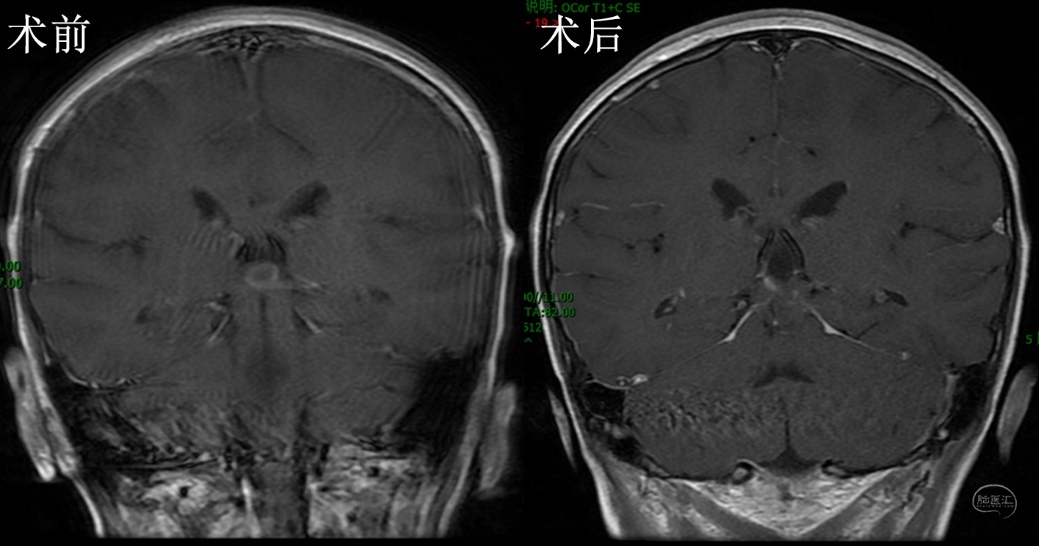

完善术前检查后,在全麻下行内镜下经幕下小脑上入路切除松果体区囊肿。俯卧位,枕下正中切口,骨窗充分暴露窦汇和双侧横窦。剪开、悬吊硬膜,经幕下小脑上探查松果体区,见囊肿位于第三脑室后部,锐性分离周围缘蛛网膜,完整切除囊肿,第三脑室结构清晰可见,保护完好(附视频)。术后MRI示囊肿消失(图2)。患儿恢复良好,无后遗症,1周出院。

图2,术后MRI检查,A、B、C分别为冠矢轴位手术前后增强MRI